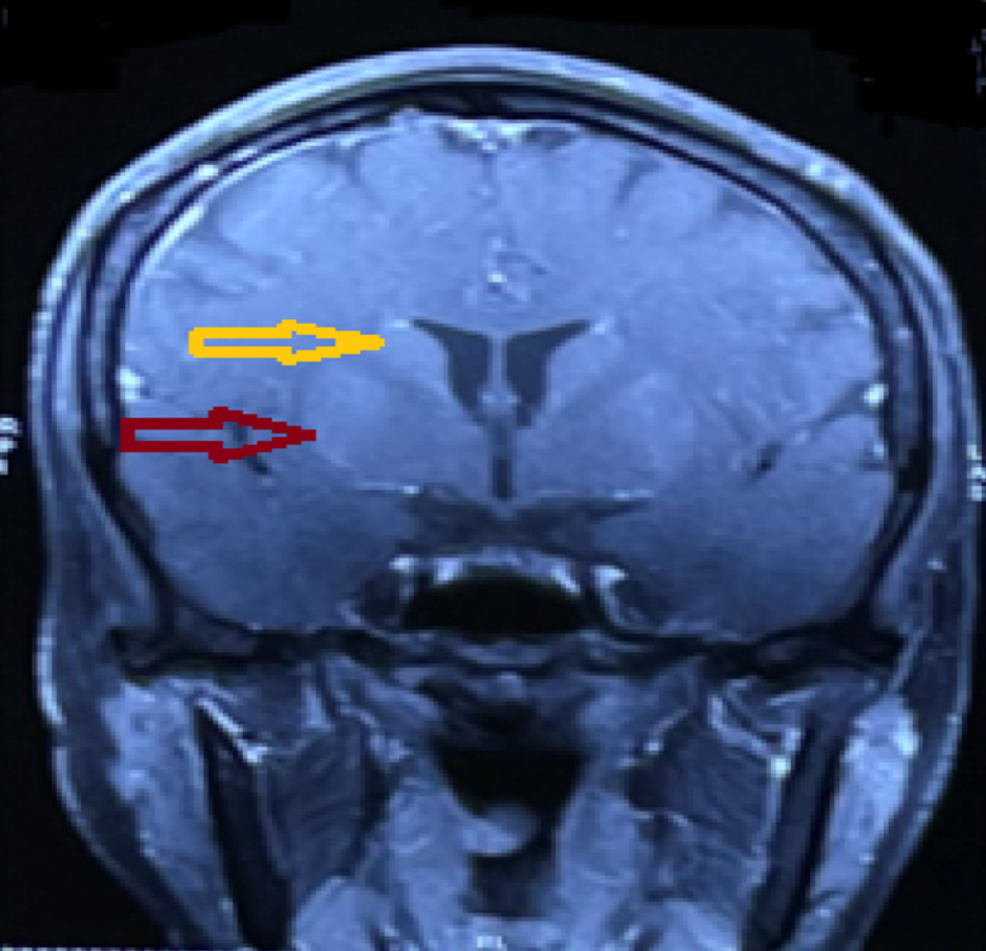

From www.researchgate.net

(A) T1weighted axial image showing hyperintensity on basal ganglia and Basal Ganglia Encephalitis Test Csf antibody assay appears to be more specific, consistent, and reliable than serum testing for autoimmune encephalitis arising. Mayo clinic is working to improve outcomes for individuals with autoimmune encephalitis, an often complex disease that can cause persistent cognitive and physical deficits. The inflammation interferes with basal ganglia functions, leading to a variety of behavioral, psychiatric, and neurologic symptoms. Involvement. Basal Ganglia Encephalitis Test.

A, B Brain MR imaging showing basal ganglia T2 hyperintense (A) and T1 Basal Ganglia Encephalitis Test The inflammation interferes with basal ganglia functions, leading to a variety of behavioral, psychiatric, and neurologic symptoms. Encephalitis is a severe inflammatory disorder of the brain with many possible causes and a complex differential diagnosis. Involvement of the thalamus or basal ganglia (t/bg) occurs in a subset of patients with encephalitis and may be an important. Csf antibody assay appears. Basal Ganglia Encephalitis Test.